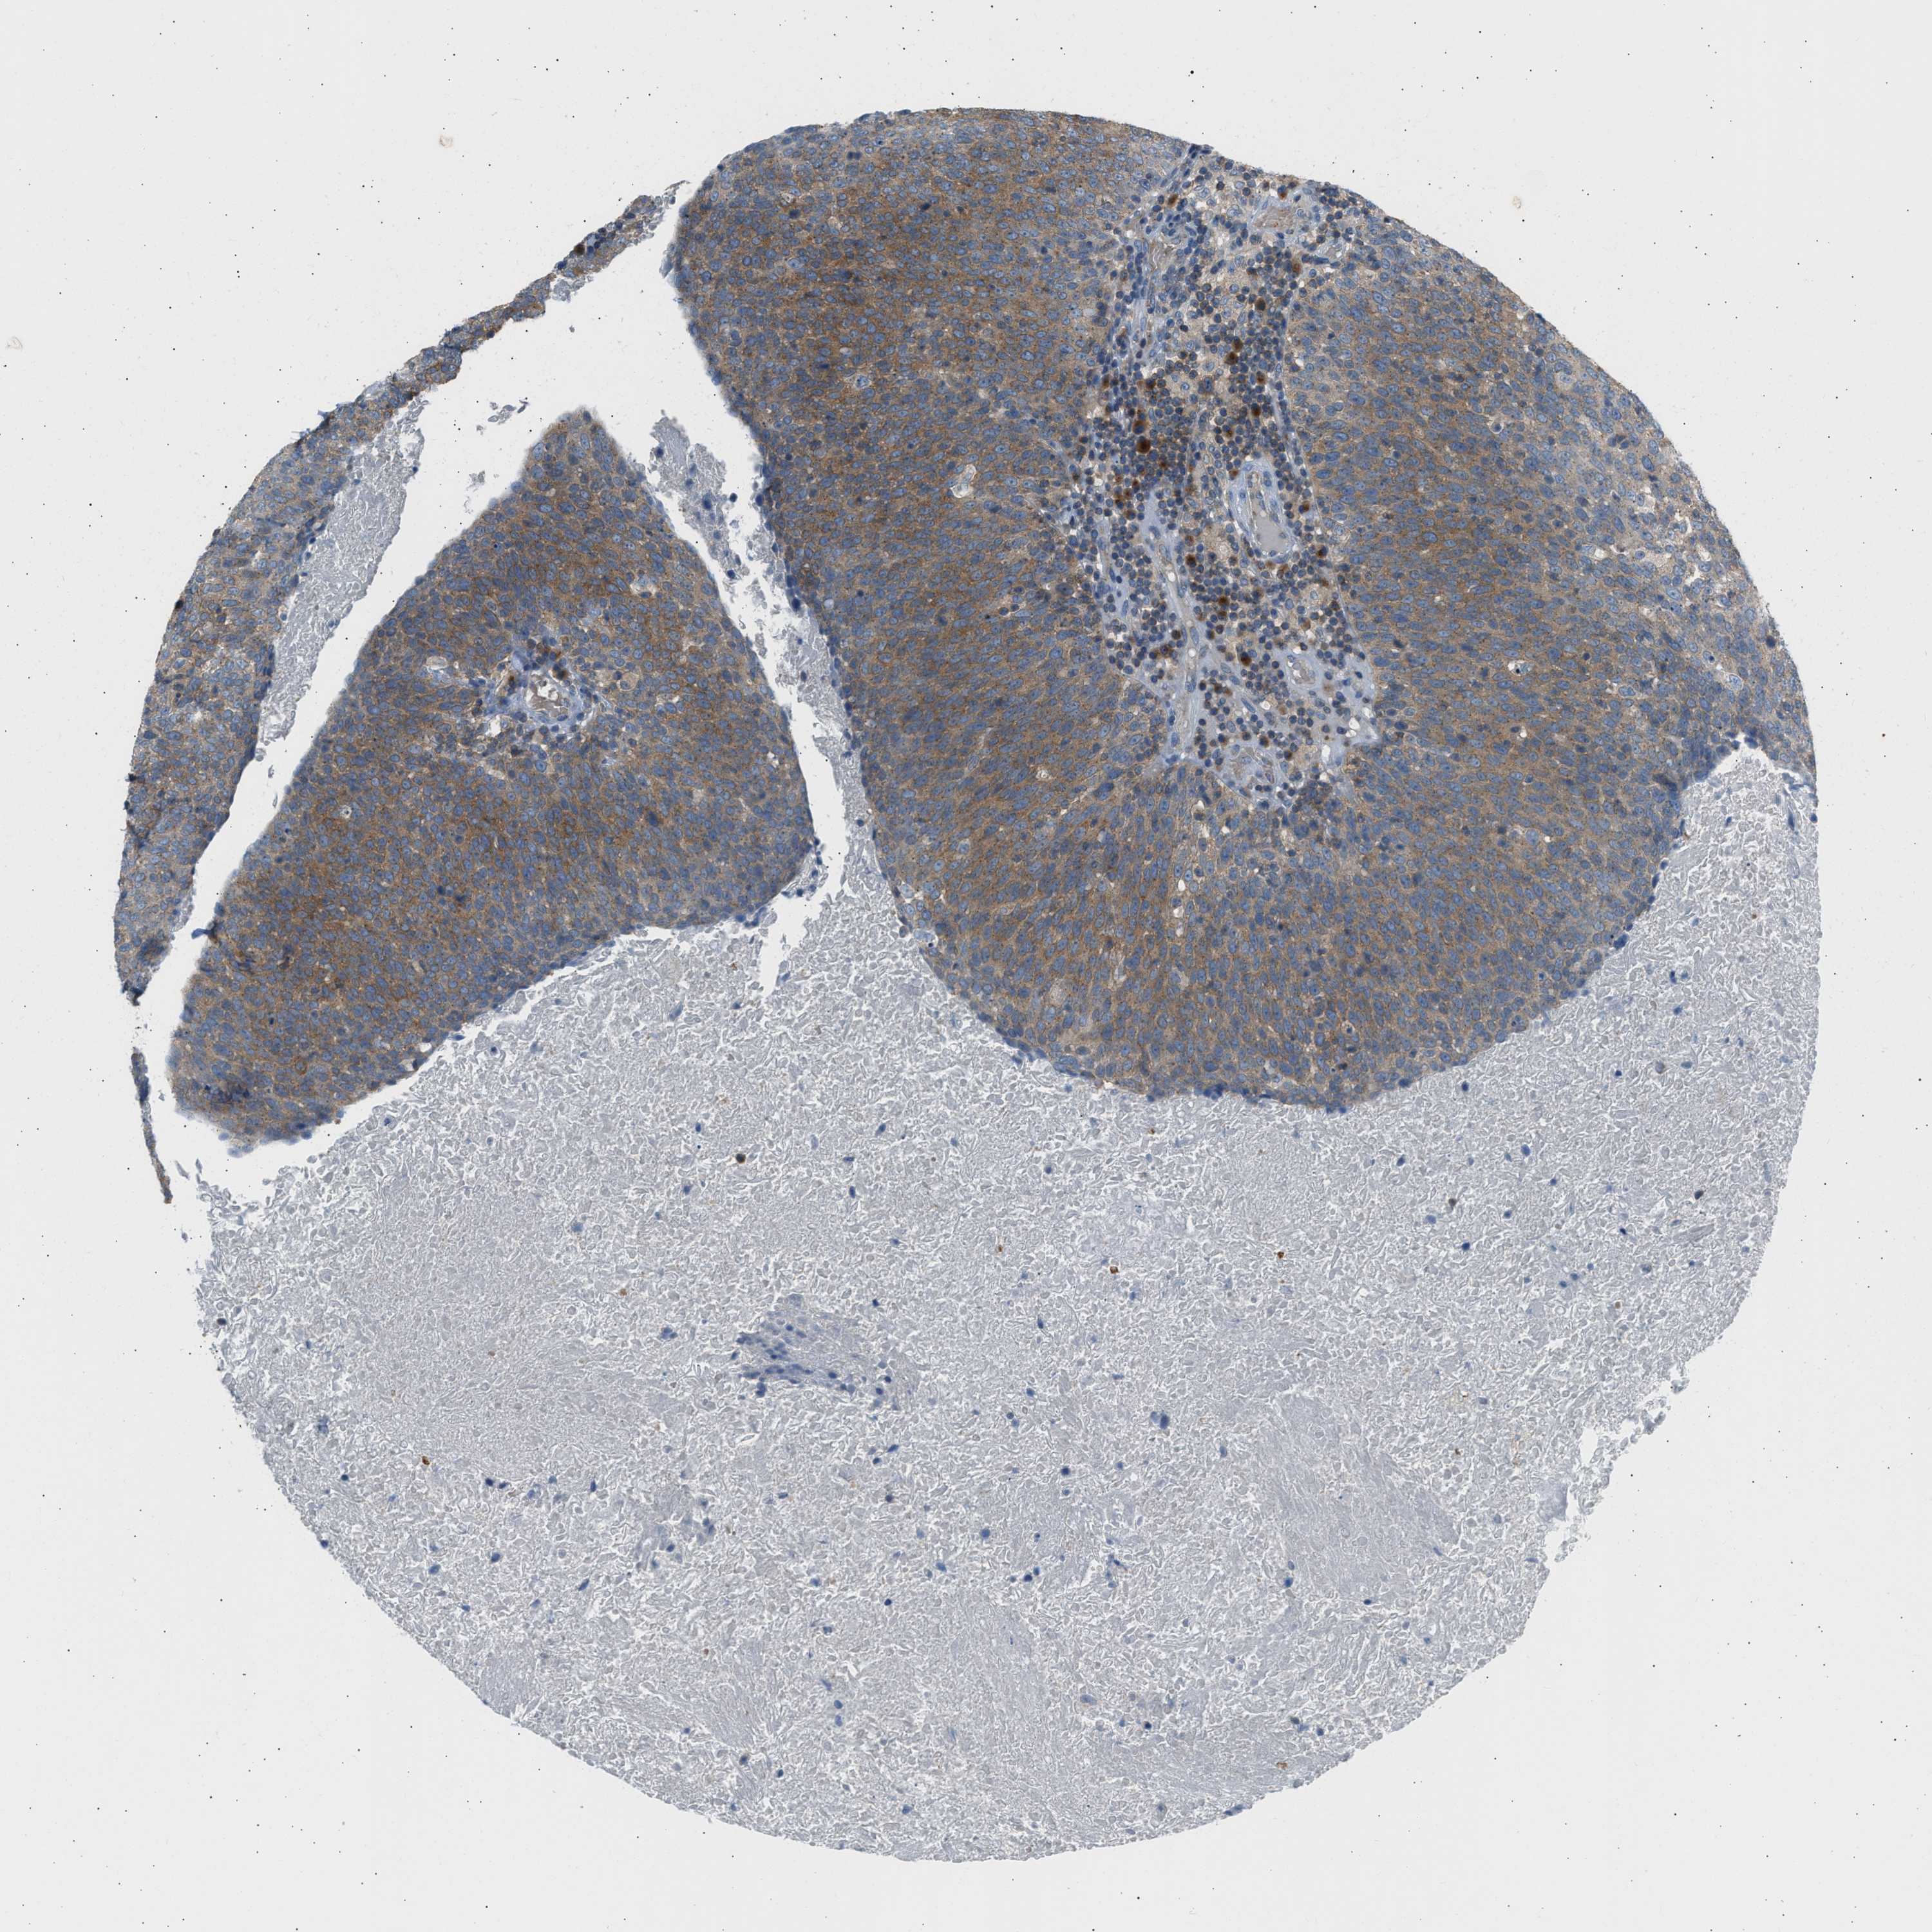

HEAD AND NECK CANCER - Protein expressioni

A mouse-over function shows sample information and annotation data. Click on an image to view it in a full screen mode. Samples can be filtered based on level of antibody staining by selecting one or several of the following categories: high, medium, low and not detected. The assay and annotation is described here.

Antibody stainingi

Antibody staining in the annotated cell types in the current human tissue is reported as not detected, low, medium, or high, based on conventional immunohistochemistry profiling in selected tissues. This score is based on the combination of the staining intensity and fraction of stained cells.

Each image is clickable and will lead to virtual microscopy that enables deeper exploration of all samples and also displays staining intensity scores, fraction scores and subcellular localization as well as patient and tissue information for each sample.

Antibody HPA019862

Staining

High

Medium

Low

Not detected

Intensity

Strong

Moderate

Weak

Negative

Quantity

>75%

75%-25%

<25%

None

Location

Nuclear

Cytoplasmic/membranous

Cytoplasmic/membranous,nuclear

Squamous cell carcinoma, NOS

Squamous cell carcinoma, metastatic, NOS

Adenocarcinoma, NOS